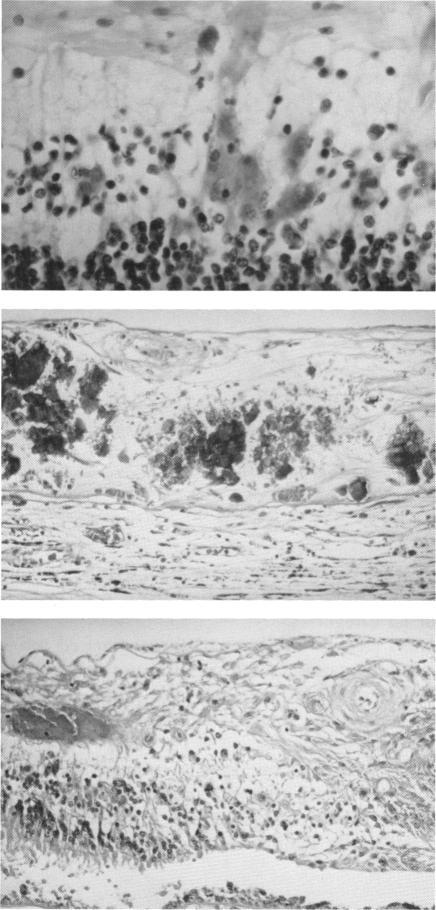

In conclusion, this clinicopathologic study has shown that CMV ocular infection is present in about 16% of terminal AIDS patients. The treatment of CMV retinitis reduces the number of CMV-infected nonocular organs and may also lessen the severity and control the spread of concurrent nonocular infection, both of which may prolong survival in AIDS patients. Other opportunistic infections, involving primarily the choroid, were also seen in a number of patients, some of whom had concurrent intraocular infections with CMV and P carinii, M avium-intracellulare, C neoformans. In addition, all of these choroidal infections were components of disseminated infection, underscoring the increasingly important role of the ophthalmologist in the diagnosis and treatment of disseminated opportunistic infections in AIDS.

总之,这项临床病理研究表明,约16%的晚期艾滋病患者存在巨细胞病毒眼部感染。巨细胞病毒性视网膜炎的治疗可减少巨细胞病毒感染的非眼部器官数量,还可能减轻并发的非眼部感染的严重程度并控制其传播,这两者都可能延长艾滋病患者的生存期。在一些患者中还可见到主要累及脉络膜的其他机会性感染,其中一些患者同时存在巨细胞病毒和卡氏肺孢子虫、鸟分枝杆菌、新型隐球菌的眼内感染。此外,所有这些脉络膜感染都是播散性感染的组成部分,这突出了眼科医生在艾滋病播散性机会性感染的诊断和治疗中日益重要的作用。